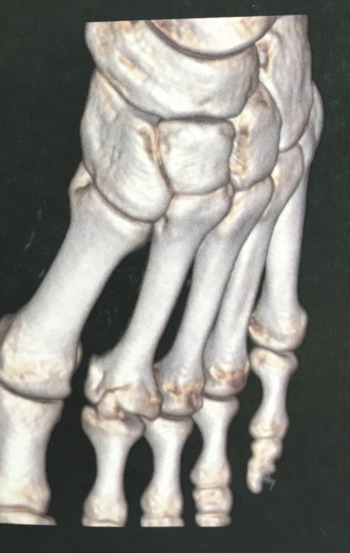

Les radiographies du pied de profil et de face (fig. 2) retrouvent une ostéocondensation, témoignant d’une hyperosotose au niveau de la tête du deuxième métatarsien, probablement séquellaire d’une ancienne fracture selon le compte-rendu radiologique. Le patient, sportif, assure n’avoir jamais eu de fracture.